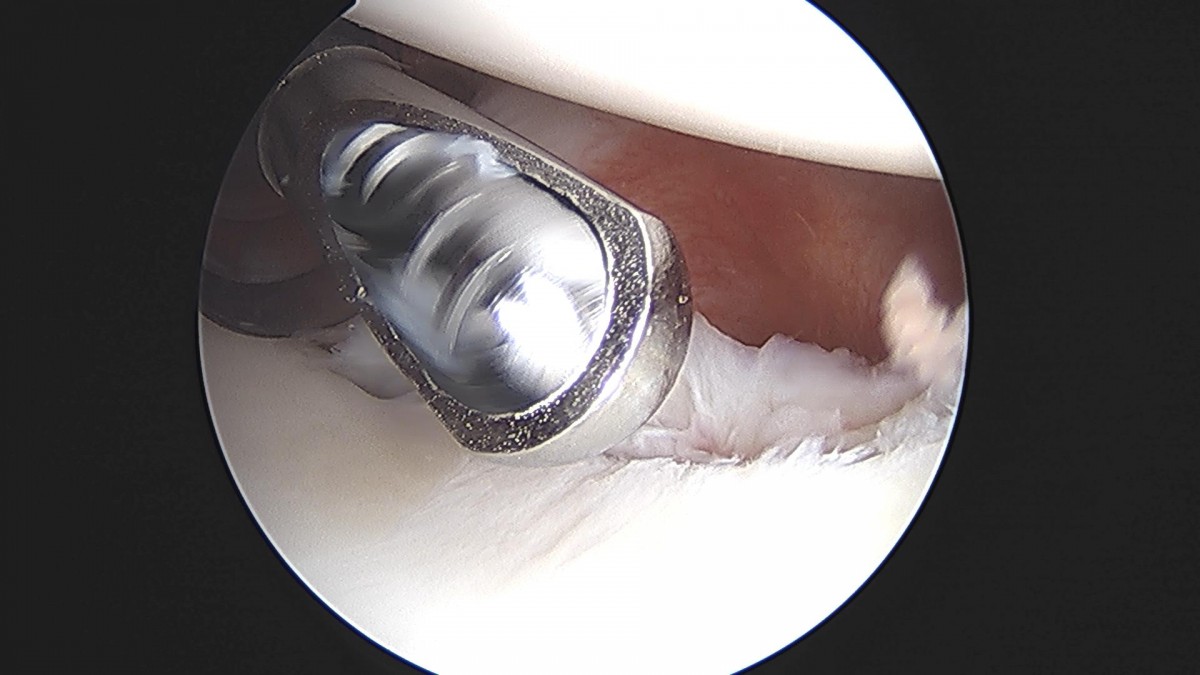

배우한원장님 어깨관절와순봉합술 (4315)유O 환자

작성자 최고관리자 댓글 0건 조회 1,291회 작성일 22-05-09 11:51